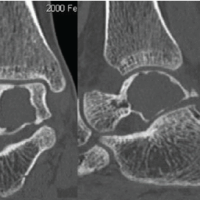

A 20-year-old female sustained trivial trauma to the left little finger, followed by acute pain, swelling, and deformity. Radiographs showed an enchondroma of the proximal phalanx complicated by a pathological fracture with cortical breach. A similar dorsal approach was employed; after curettage and grafting with olecranon cancellous bone, prophylactic K-wire fixation was used to stabilize the fracture site. Histopathology demonstrated mature cartilage with uniform chondrocytes, confirming enchondroma without evidence of malignancy. Sutures were removed at 2 weeks, and K-wires at 6 weeks, followed by physiotherapy. By 12 weeks, radiographs showed satisfactory union with graft consolidation. The patient achieved complete functional recovery, including grip and pinch strength, and resumed regular household activities without restriction.

Surgical management was undertaken in all cases. Using a dorsal midline approach, an oval cortical window was created with a low-speed drill. The tumor contents were curetted, the cavity irrigated with hydrogen peroxide and saline, and filled with morselized cancellous bone graft harvested from the ipsilateral olecranon. Prophylactic K-wire fixation was employed to maintain stability and prevent post-operative fracture (Fig. 2). The excised tissue was sent for histopathological evaluation, which confirmed the diagnosis of enchondroma.

Sutures were removed at 2 weeks. Physiotherapy was initiated after K-wire removal to prevent stiffness. Radiographs at 6 and 12 weeks demonstrated consolidation of grafts and obliteration of cavities (Fig. 3). All patients regained full range of motion and resumed normal activities without recurrence or complications.